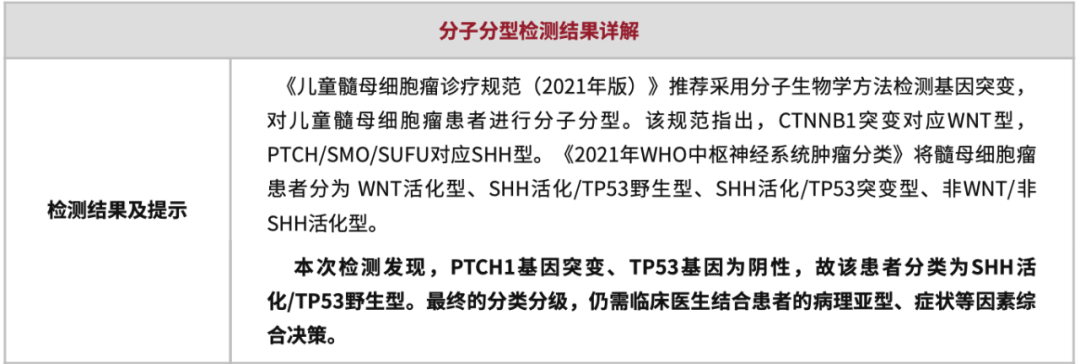

手术后病理和分子分型

1.该肿瘤为一种特殊类型的髓母细胞瘤,作为小儿神经外科医生,应该对此有所了解,是一个手术前应该可以知道大体病理、分子分型和临床预后的肿瘤;患儿的CT/MRI会有特殊的临床表现,CT为高密度,MRI强化明显,而且呈现一种特殊的“葡萄样”形态。该“葡萄样”形态,是这种髓母细胞瘤的特色表现。手术后病理和分子分型也证实了我们的判断。

2.该髓母细胞瘤,大体病理为“广泛结节形成型髓母细胞瘤”,分子亚型为SHH亚型,最常见的基因突变为PTCH1、SUFU、SMO等基因。其中PTCH1基因突变的临床预后最佳,SUFU基因突变的临床预后略差。该类型肿瘤治疗以化疗为主,究竟是否放疗,目前还没有定论。目前已经有针对SHH亚型的靶向药物,但是有一定的并发症,儿童髓母未常规使用。

4.该肿瘤一定的遗传概率,即所谓的Gorlin综合征,需要对患儿、患儿父母进行遗传病学筛查,进行血液检测,排除PTCH1/SUFU等基因的胚系突变。